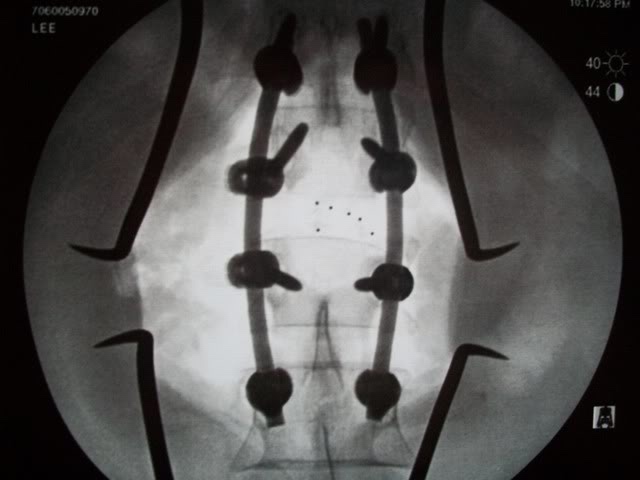

Food for thought, Buster......Yep I’m screwedI’ve got screws and rods in a wrist, elbow, shoulder and spine. I’ve given up swimming for fear of sinking due to all the metal in me. No way I’ll quit riding, though.